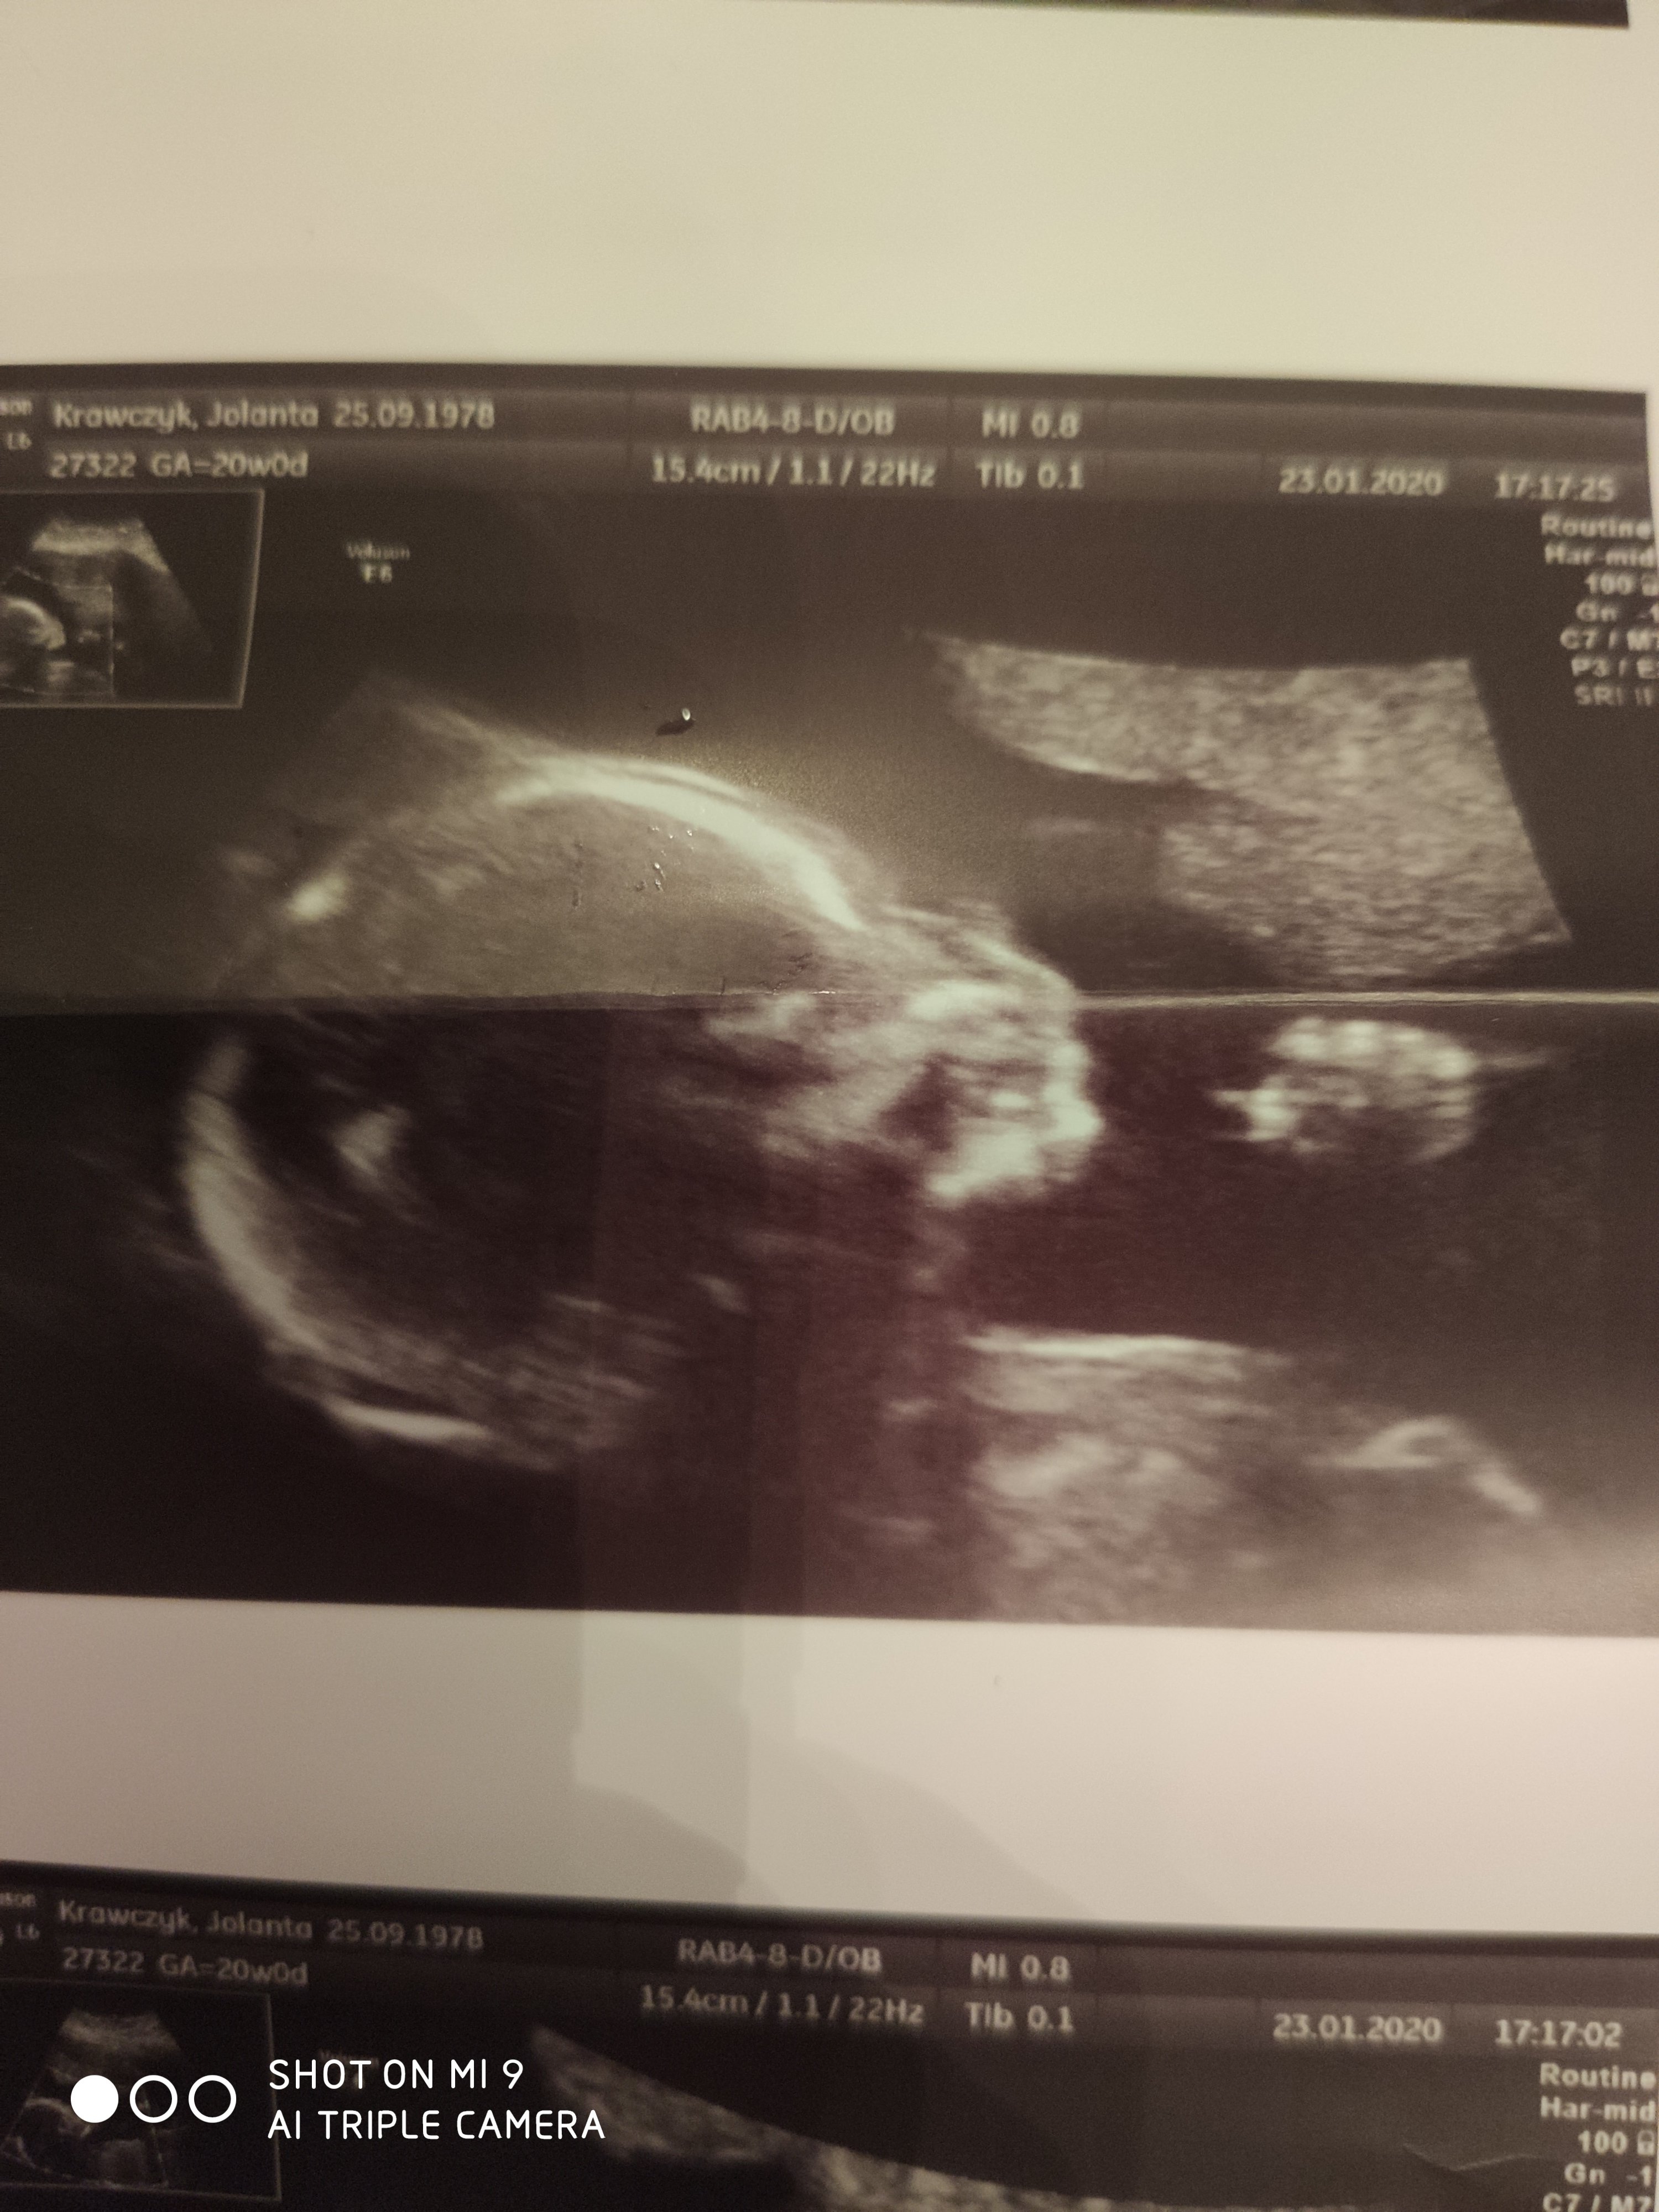

Jedno z pierwszych badań a drugie te z rączką to drugie gdzie niby nie widac